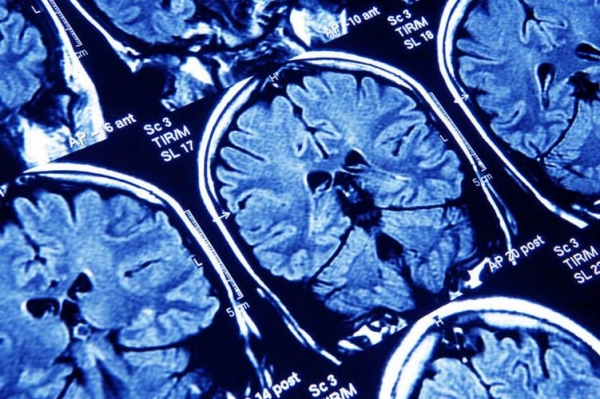

还有一种手麻,是由于脑血管问题引起的。如果突然出现单侧手麻、伴有口角歪斜、说话不清,这时候可不是神经压到这么简单,很可能是短暂性脑缺血发作,也就是"小中风"。

有数据表明,每年约有300万人发生脑卒中,而其中三成以上的人,在发病前都有类似手麻的预警。

这个信号不痛不痒,但代表着脑部某个区域供血已经出了问题,再不干预,真正的卒中可能就在几周内发生。